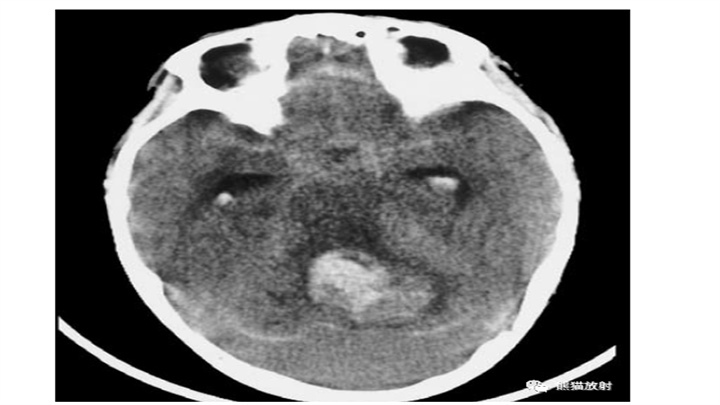

脑干血肿,向上播散至丘脑。